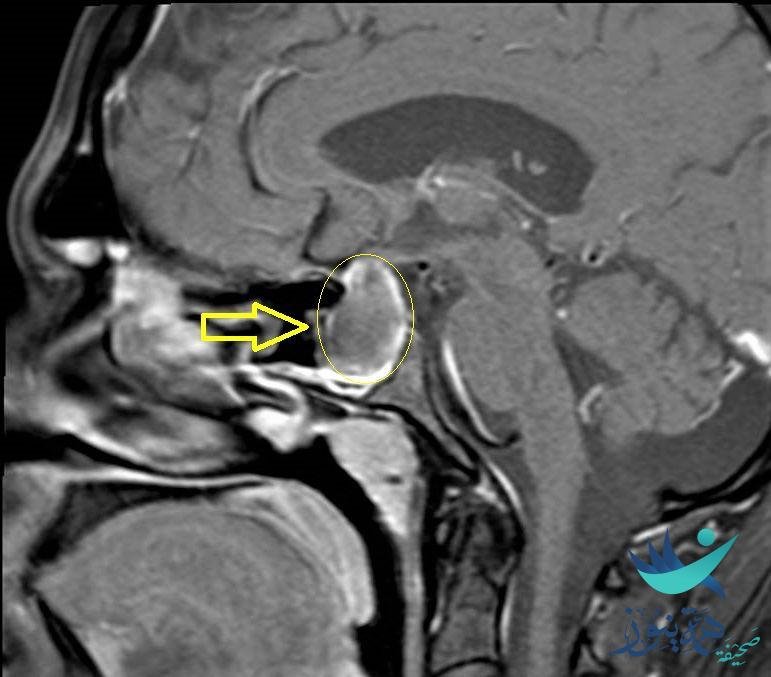

وتمكّن الفريق الطبي المكون من جراحة المخ والأعصاب والعمود الفقري بالتعاون مع قسم جراحة الأنف والأذن والحنجرة، من استئصال ورم حميد في قاع الجمجمة لمريض في العقد الثالث من العمر، وذلك عن طريق الأنف بمساعدة منظار جراحي لا يتعدى قطره (3) مليمتر، والوصول إلى الغدة النخامية واستئصال الورم بدون شق جراحي خارجي.